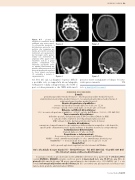

Figure 4-7 - L’esame TC eseguita in condizioni basali evidenzia una estesa raccol- ta extra-assiale ipodensa, a distribuzione pressoché sim- metrica, che comprime en- trambi gli emisferi encefalici inducendo uno spianamento dei fisiologici solchi perien- cefalici con incremento di ampiezza dello spazio inter- emisferico (5,6,7). Il grave quadro, compatibile con ematoma sub-durale croni- co, appare ulteriormente ag- gravato dalla presenza di una quota di iperdensità mediana in fossa cranica posteriore (7), ascrivibile a recente ri- sanguinamento.

Figura 4

Figura 5

Figura 7

Figura 6